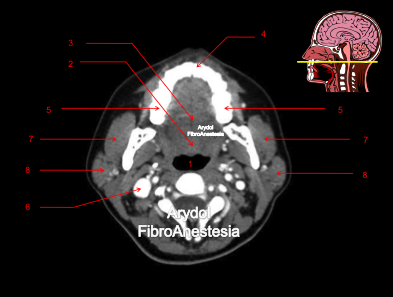

CORTE A NIVEL DEL BORDE ALVEOLAR DEL MAXILAR SUPERIOR

1.orofaringe; 2.paladar blando; úvula; 3.musculatura intrínseca lengua; 4. borde alveolar maxilar sup; 5.rama mandibular; 6.vena yugular interna; 7.músculo masetero; 8.glándula parótida